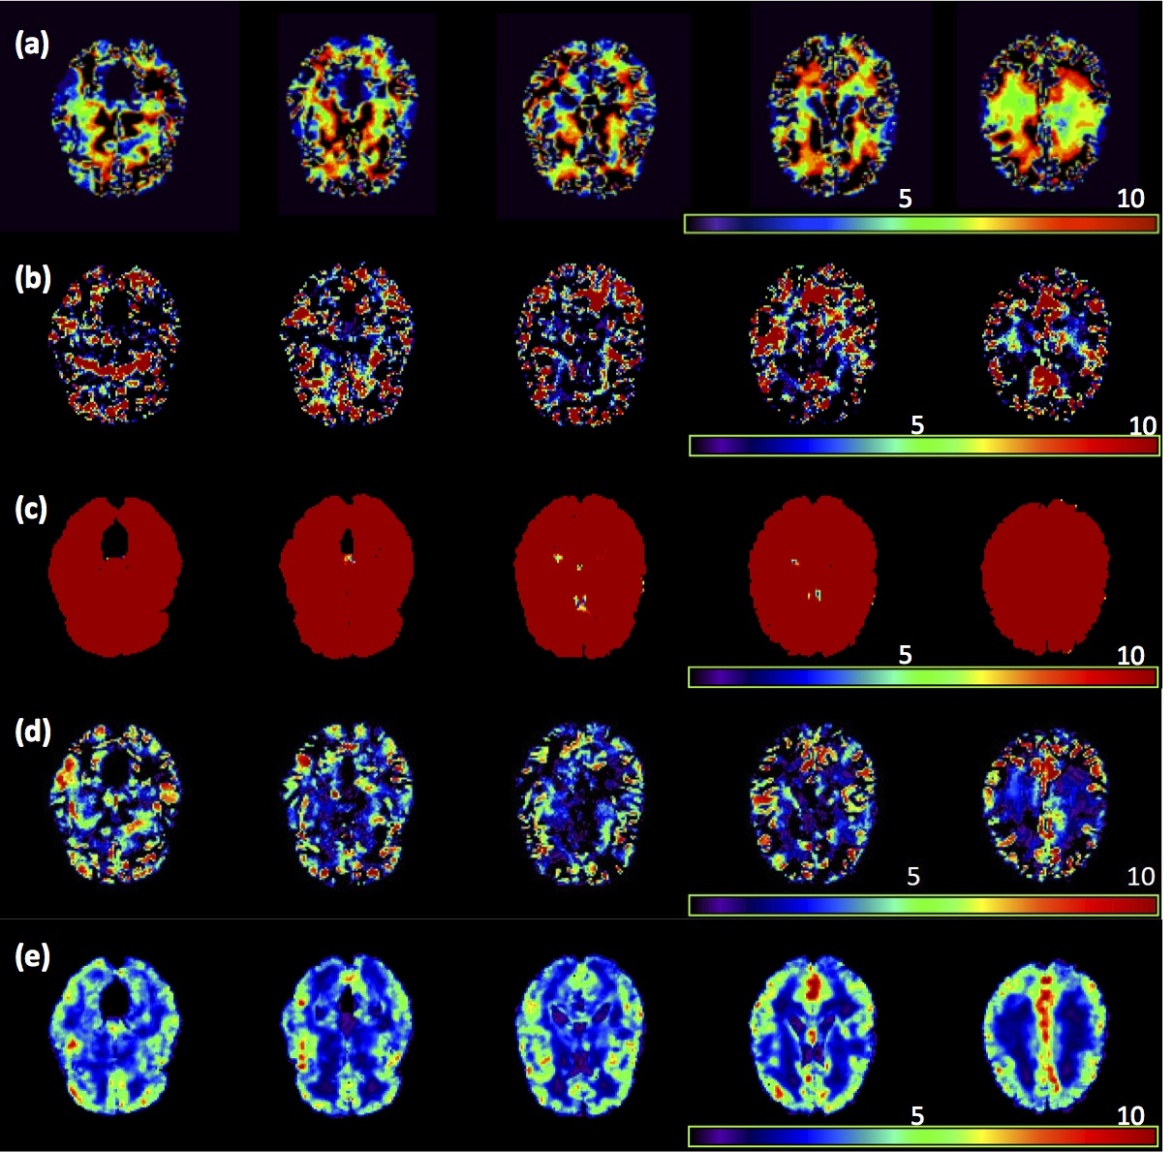

We chose different pattens for different images in order to examine the finite sample performance of our estimation method under different scenarios. We set all the slices along the coronal axis to be identical for each of images. As shown in Figure 4, each slice of the three different images has four different blocks and 5 different regions of interest (ROIs) with varying patterns and shape. The true values of were varied from to , respectively, and were displayed for all ROIs with navy blue, blue, green, orange and brown colors representing and , respectively.

We fitted the SVCM model (1) with the same set of covariates to a simulated data set, and then applied the three-stage estimation procedure described in Section 2.2 to calculate adaptive parameter estimates across all pixels at 11 different scales. In MASS, we set for . Figure 4 shows some selected slices of at (middle panels) and (lower panels). Inspecting Figure 4 reveals that all outperform their corresponding in terms of variance and detected ROI patterns. Following the method described in Section 2.2, we estimated based on the residuals by using the local linear smoothing method and then calculate . Figure 3 shows some selected slices of the first three estimated eigenfunctions. Inspecting Figure 3 reveals that are relatively close to the true eigenfunctions and can capture the main feature in the true eigenfunctions, which vary in one direction and are constant in the other two directions. However, we do observe some minor block effects, which may be caused by using the block smoothing method to estimate .